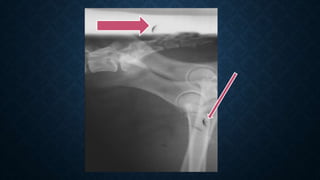

UBERSCHWINGER OR REBOUND EFFECT

• Also called as Halo effect.

• Around the metal or areas where there is a large density

UBERSCHWINGER OR REBOUNDEFFECT • Also called as Halo effect. • Around the metal or areas where there is a large density difference between adjacent objects.